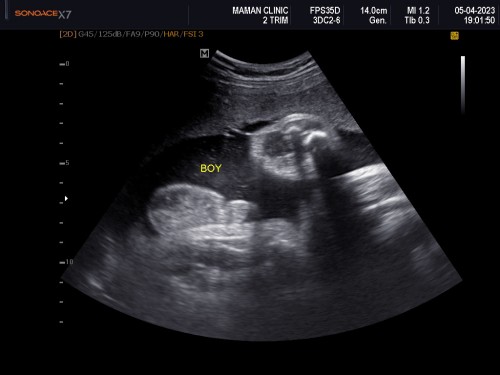

คุณหมอบอกน้องเป็นผู้ชาย อยากทราบว่าดูจากตรงไหนดูไม่ออกเลยคะ ดูไม่ออกจริงๆ

กลม ๆ ล่างคำว่า boy ค่ะ ไข่กับจู๋แบบซูมสุด ๆ ชัดเจน